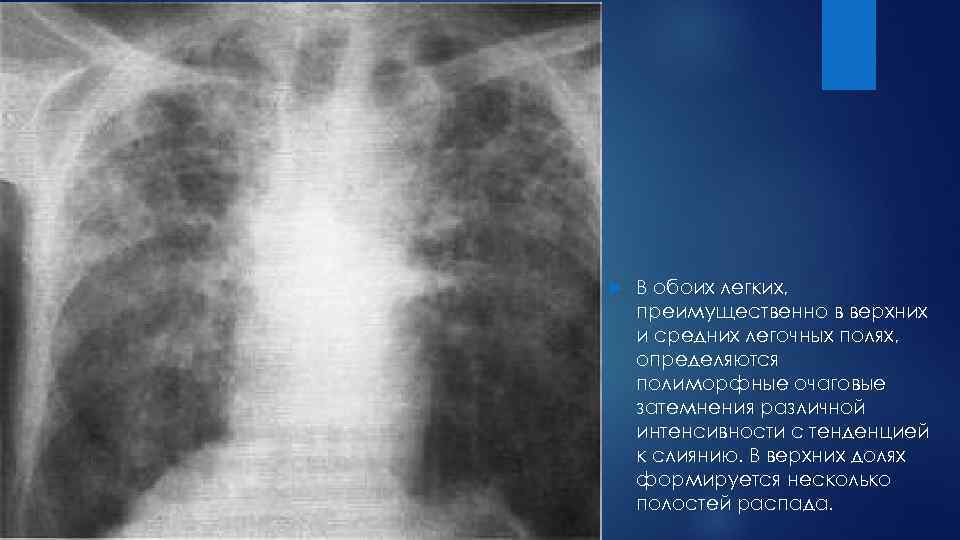

Иллюстрации по теме очагового и инфильтративного туберкулеза